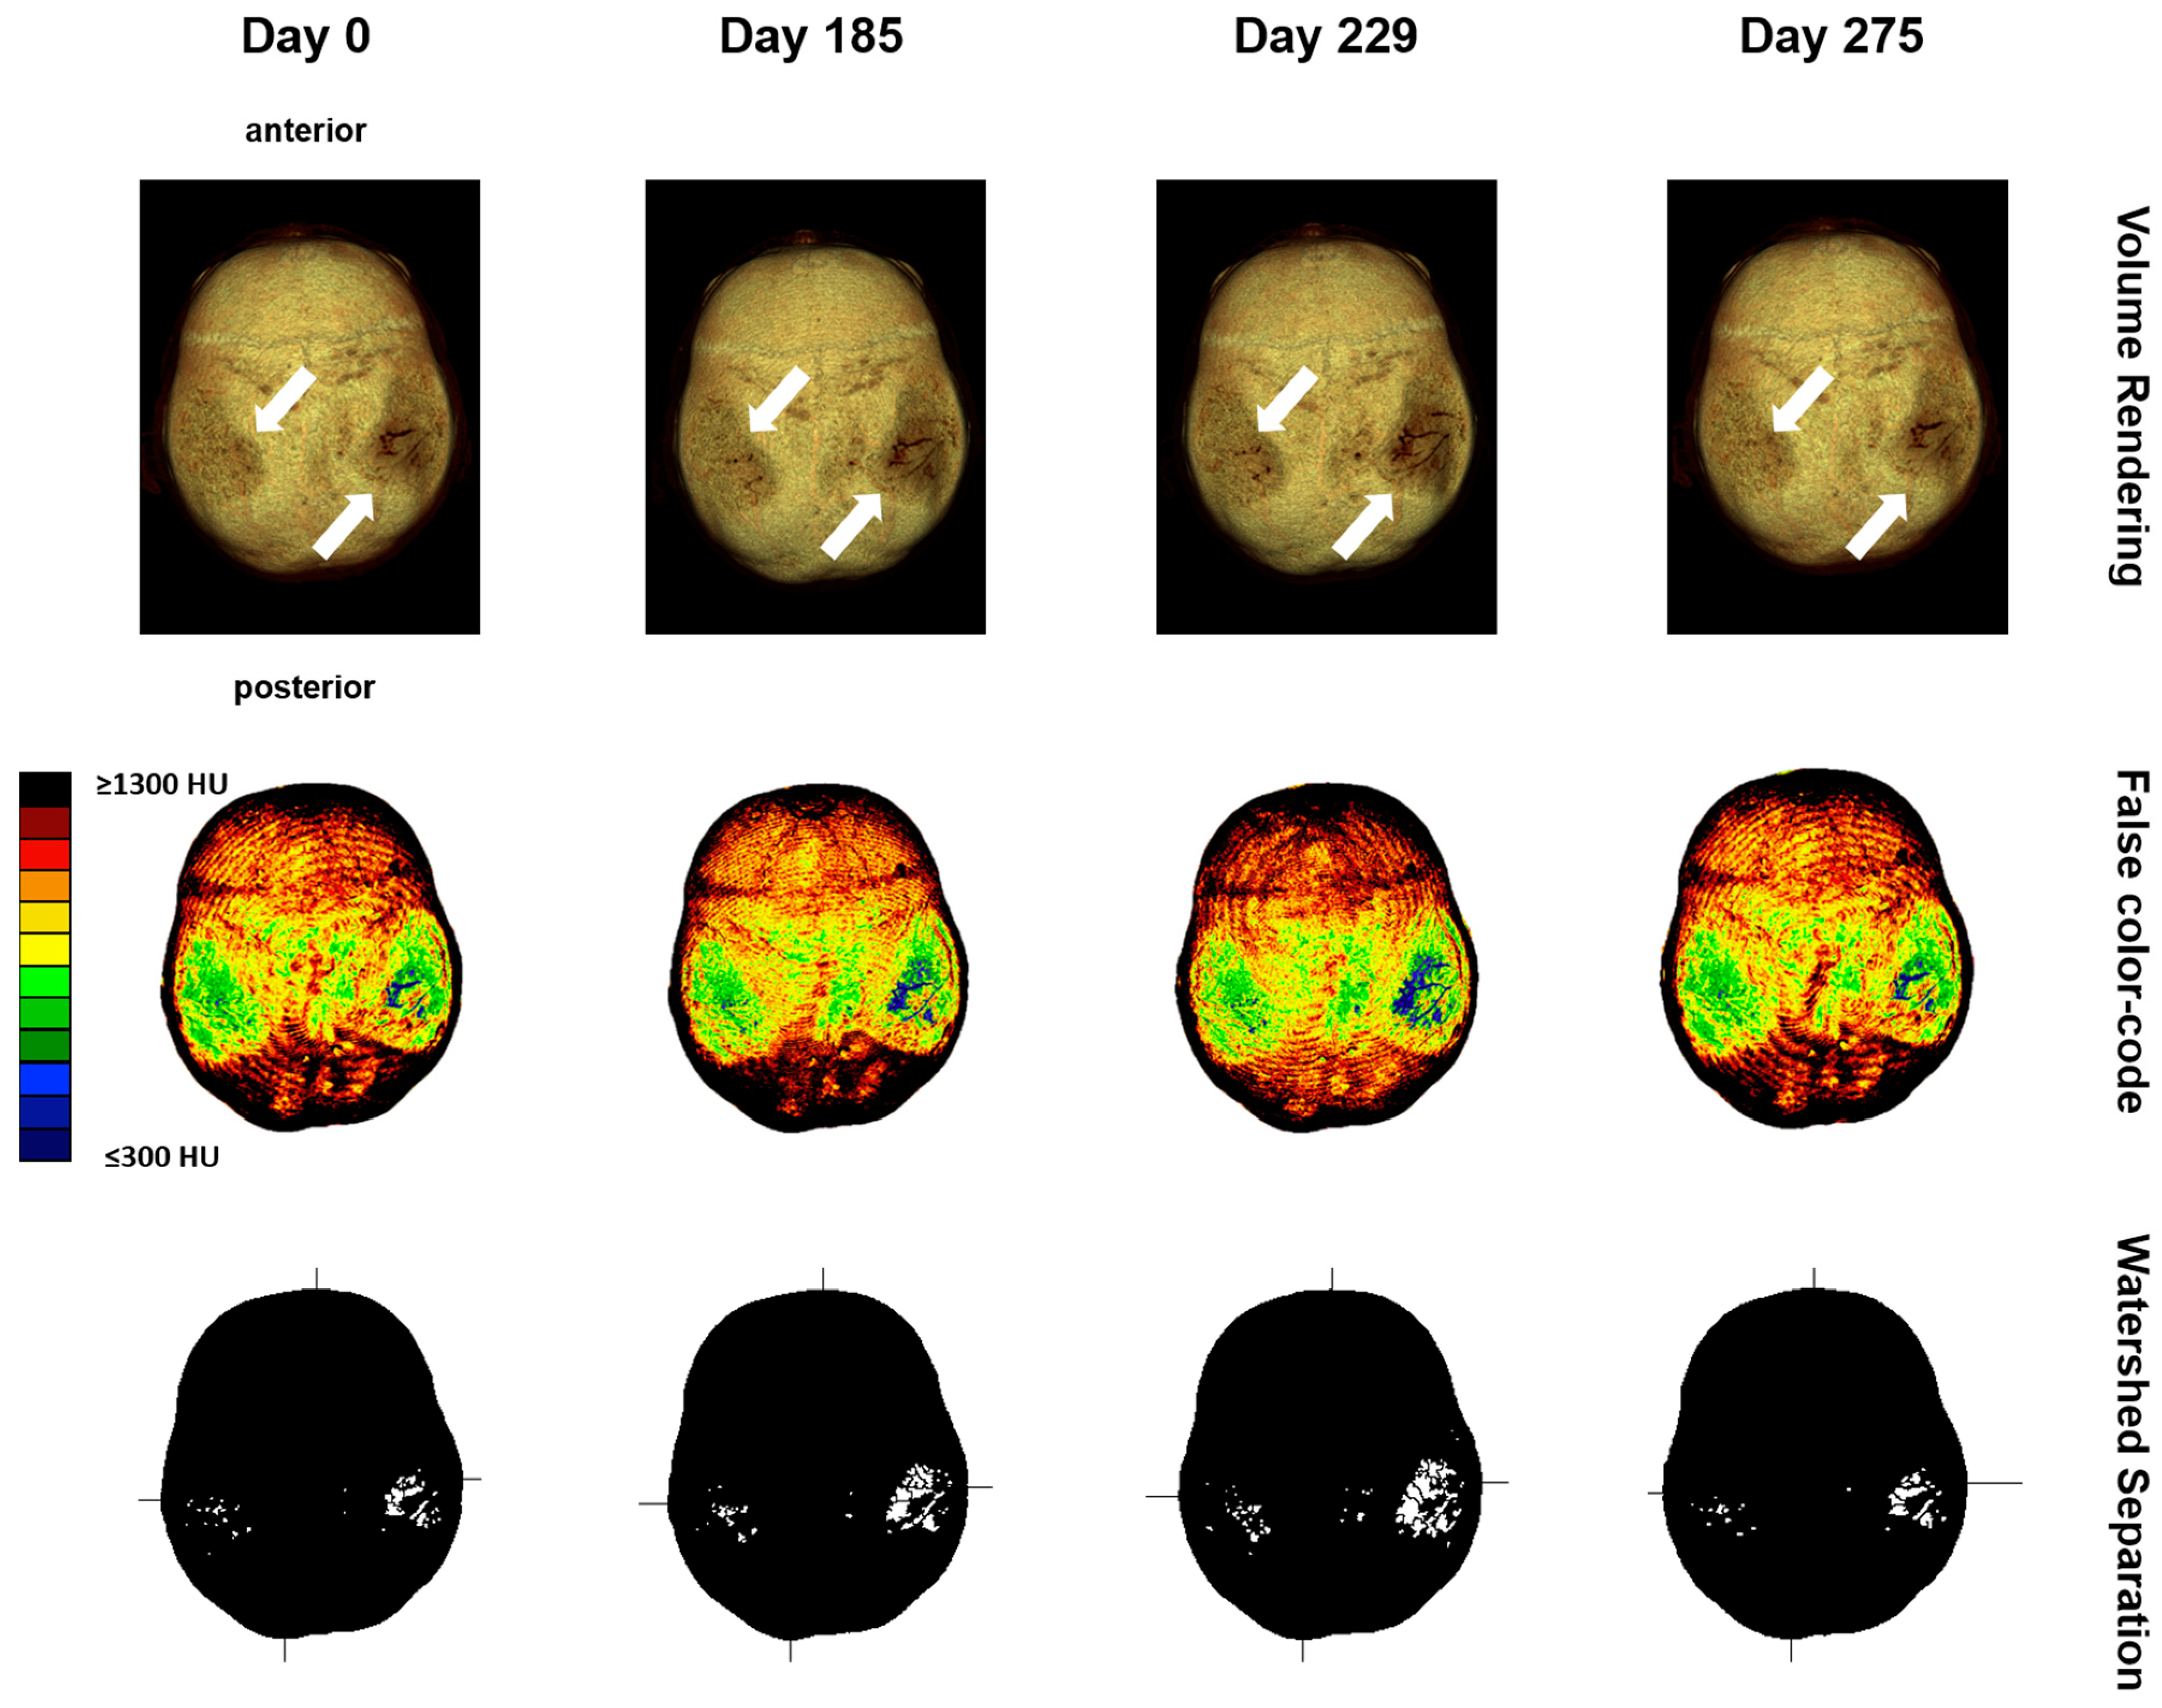

2.2.2. Computed Tomography Osteoabsorptiometry

2.2.3. Analysis of Densitogram Patterns

3.2. Descriptive Imaging Reports before and after 3D Reconstruction

3.3. Two-Dimensional (2D) Measurements of Biparietal Thinning